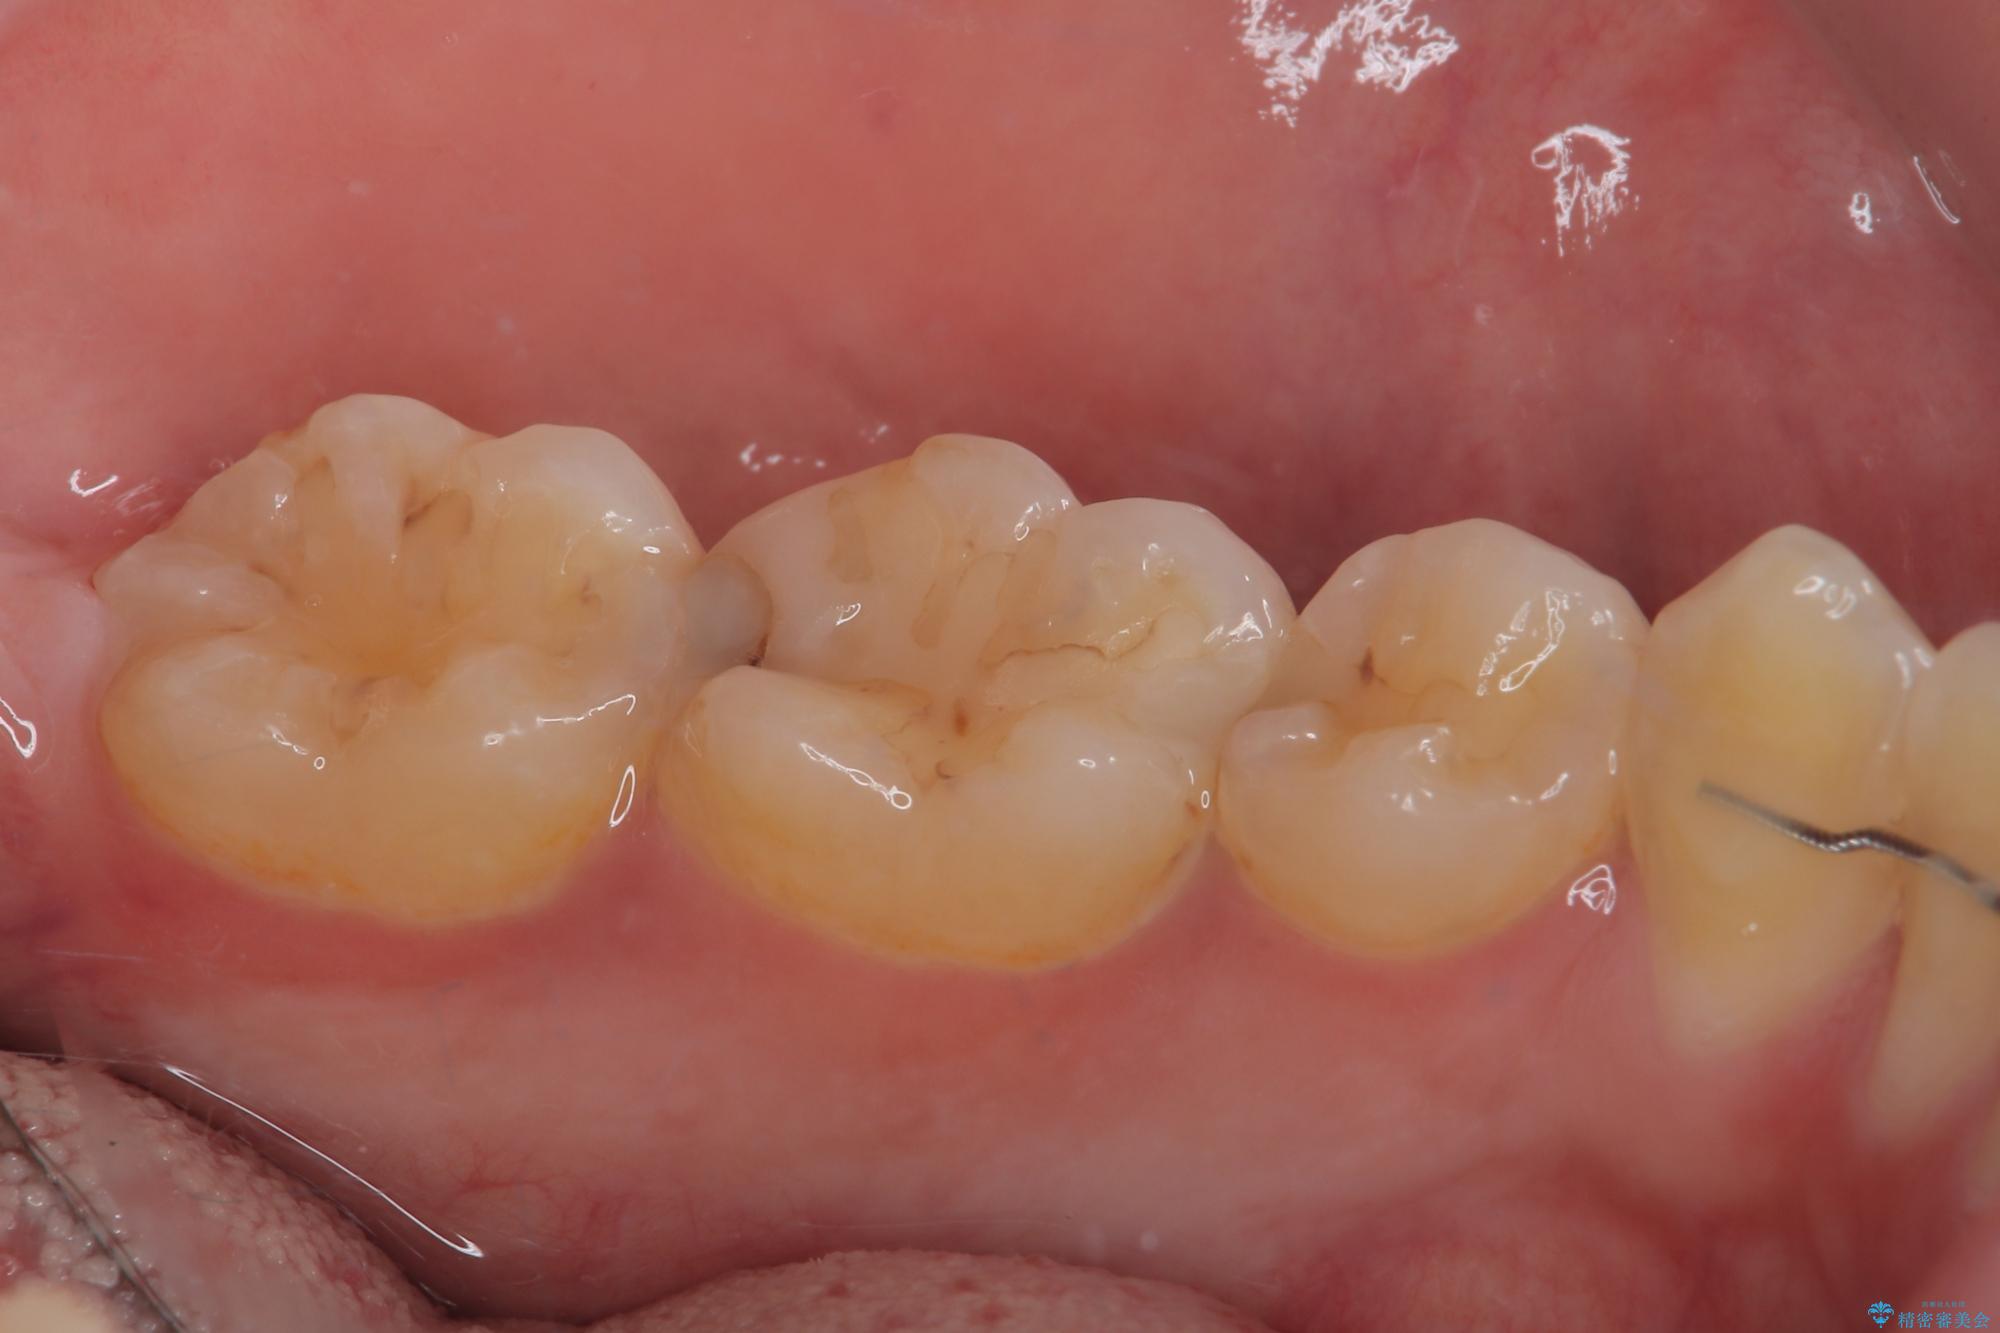

虫歯による不快な症状がなくなり喜んでいただきました。セラミックの被せものが入った後の違和感なく過ごせているそうです。矯正治療終了直後の被せもの治療なのでリテーナーの作成回数をできるだけ少なく迅速に行うことを考慮して治療を行いました。

今後、ホワイトニングを行う予定なので、患者様のご希望により、周りの歯に比べてあえて白い被せものを作成しました。